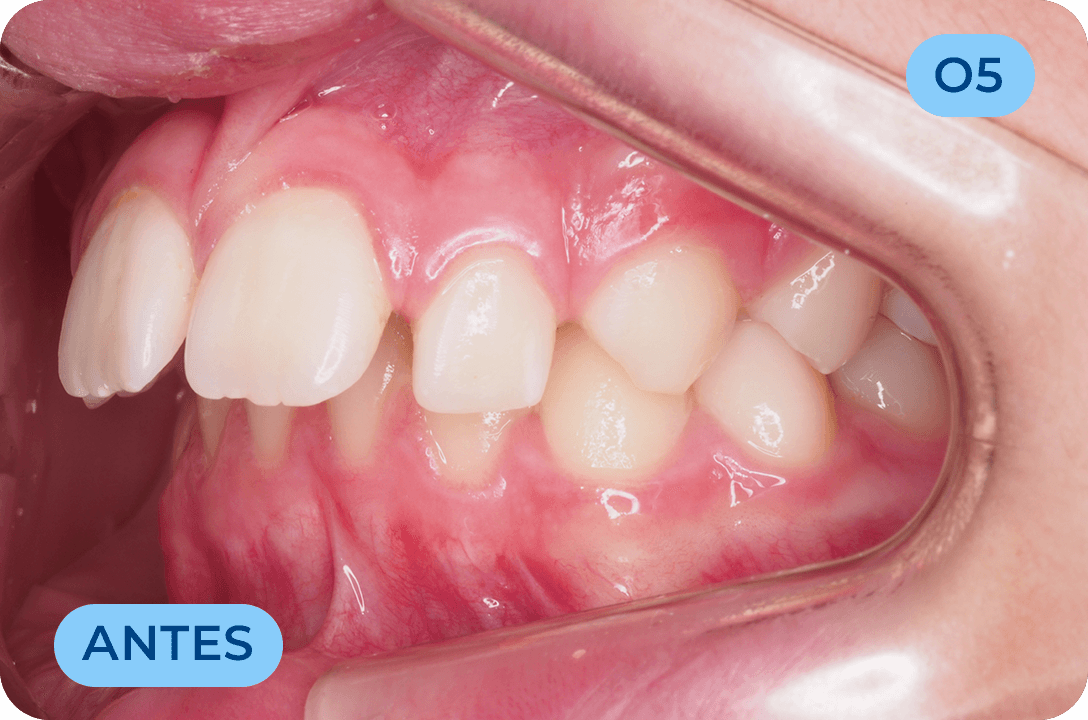

Ortodontia Invisível

A Ortodontia Invisível é uma especialidade da Medicina Dentária que se debruça sobre o estudo e correção das más posições dentárias e dos maxilares, através de um método totalmente inovador. Tal como o nome indica, este sistema de correção elimina a necessidade de utilizar os materiais habitualmente associados aos aparelhos fixos metálicos. A Clínica Dr. Fernando de Paiva orgulha-se de ser uma pioneira a nível nacional a ter disponíveis os alinhadores invisíveis Spark.